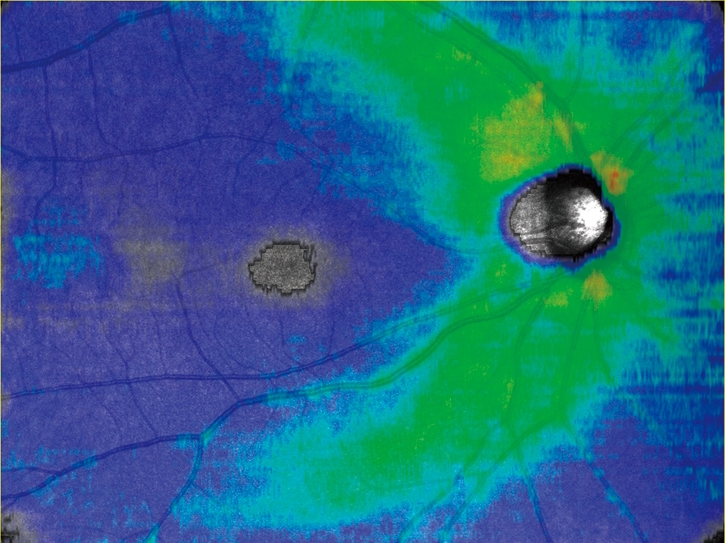

任意設定により5種類(初期設定:網膜全層、表層、深層、外層、脈絡膜)のパノラマが同時に自動合成できます。

網膜全層 HD4 4.5×4.5mm 6枚 パノラマ |

網膜表層 |

網膜深層 |

網膜外層 |

脈絡膜 |